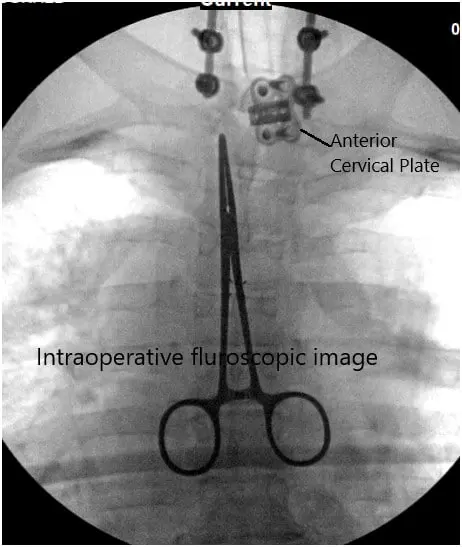

Fluoroscopy was used to localize our region of interest and then prepped and draped the patient’s cervicothoracic region. Call to order was completed and perioperative antibiotics were dosed intravenously. At this point, we made an incision with the #10 blade down to the subcutaneous fat and thereafter followed a midline avascular plane with the Bovie cautery down to the spinous processes.

We used the McCulloch retractors to this. We then employed fluoroscopy once again to ensure our level of operation and we were able to confirm the C7 level by the visualization of previous instrumentation to that level.

Intraoperative fluoroscopic image.